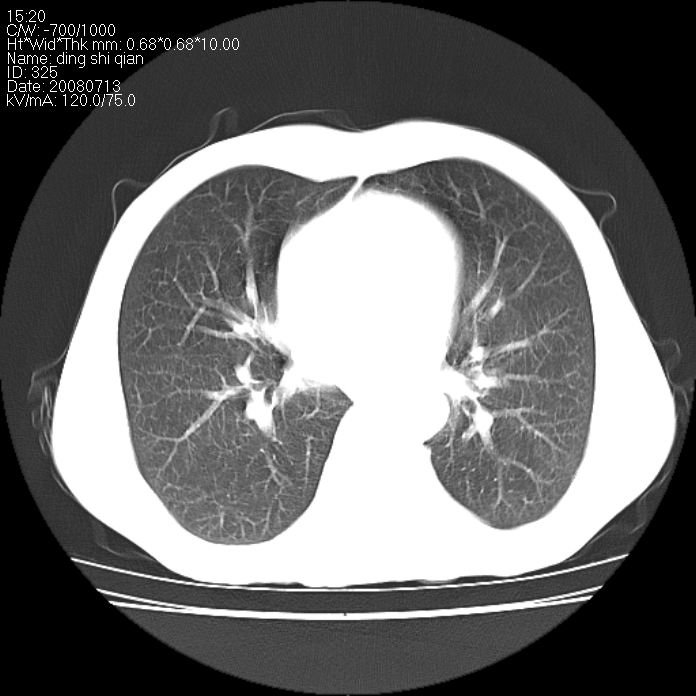

标题: CT14654:男 50岁 近来胸痛 [打印本页]

标题: CT14654:男 50岁 近来胸痛

右侧上肺块状软组织影,浅分叶,边缘毛刺证,与胸膜粘连,考虑:周围性肺癌

右侧上肺块状软组织影,浅分叶,边缘毛刺证,与胸膜粘连,考虑:周围性肺癌!支持!